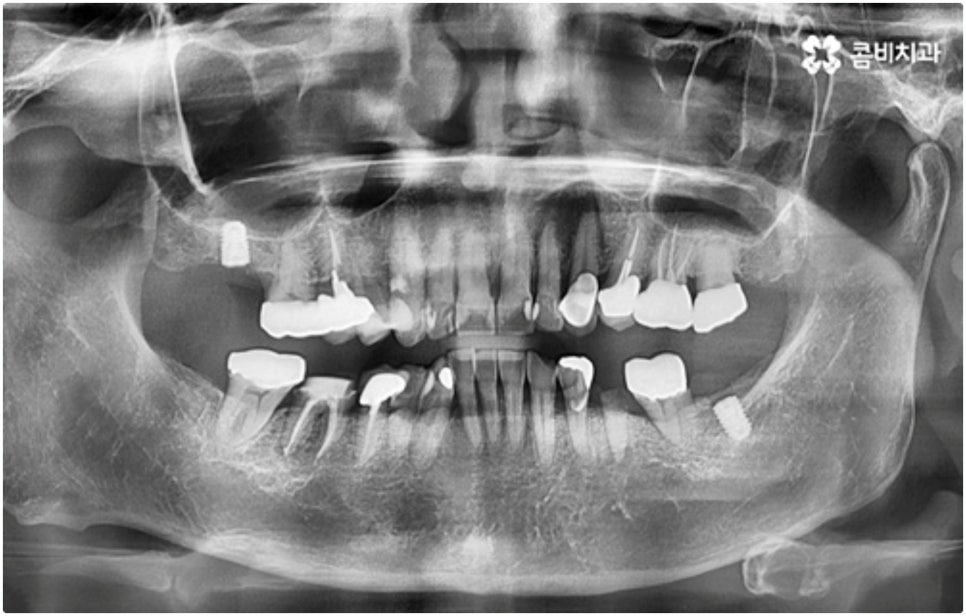

모든 치아가 위치와 모양이 제각각 다른데 특히 어금니는 구강 내 깊은 곳에 있고 주름진 저작면을 가지고 있기 때문에 관리할 때 더욱 주의할 필요가 있습니다. 꼼꼼하게 칫솔질을 해준다고 해도 음식물 찌꺼기가 남게 될 가능성이 높아 충치나 치주염 등 구강 질환이 빈번하게 발생할 수 있기 때문인데요, 이때 빠른 발견으로 초기 대처를 해주지 못하면 내부 신경까지 손상이 깊어져 치아를 발치하고 어금니임플란트 시술을 받아야 할 상황까지 발생할 수 있어요.

임플란트 시술이 환자분들의 잇몸뼈에 직접 고정을 시키는 방법인 만큼 개개인의 치주 상태, 구강 내부 구조 등을 면밀하게 살펴보고 치료 계획을 세워야 하며 그 밖에도 치아가 빠진 지 얼마의 시간이 흘렀는지, 장기적으로 복용 중인 약이 있는지 등 영향을 줄 수 있는 모든 관련 상황을 종합적으로 고려하여 환자분들에게 딱 맞는 어금니임플란트 시술을 무리하지 않게 진행하는 것이 중요한 체크 포인트라고 할 수 있는데요. 그렇기 때문에 먼저 3D CT를 이용한 정밀한 검사를 통해 어떤 종류의 임플란트를 어떻게 진행할지 신중하게 검토해야 하며 또한 풍부한 노하우와 뛰어난 기술력을 갖추고 있는 의료진과 함께 충분한 사전 상담을 하실 필요가 있습니다.

이와 같이 상악의 경우 상악동과 비강저(콧구멍 바닥)까지의 거리 및 신경과 혈관분포, 하악의 경우 하치조 신경 및 하치조관과 이공까지의 거리, 주위 조직 등에 대한 면밀한 검진과 파악이 필요하기 때문에 임플란트 시술을 진행할 때 상하악골 및 주변 조직을 해부학적으로 자세히 체크할 수 있는 정밀 장비 및 담당 의료진의 숙련도가 굉장히 중요한 요소라고 할 수 있어요.